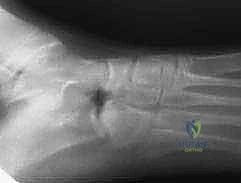

* Plain Radiographs: These are our first line. We obtain AP, lateral, 45-degree oblique, and axial views of the foot.

* The 45-degree oblique view is the workhorse for identifying a calcaneonavicular coalition. You might see a discrete bony bridge, or, more subtly, an extended, narrow beak of bone projecting from the anterior process of the calcaneus towards the navicular – this is the classic "anteater sign."

* Axial View: Crucial for ruling out a concomitant talocalcaneal coalition, which would significantly alter our surgical plan.

• Fluoroscopic Confirmation: Now, bring in the C-arm. Obtain AP and lateral radiographs to confirm the adequacy of the resection. We are looking for a clear, wide gap between the calcaneus and navicular, ensuring no residual coalition.

Image